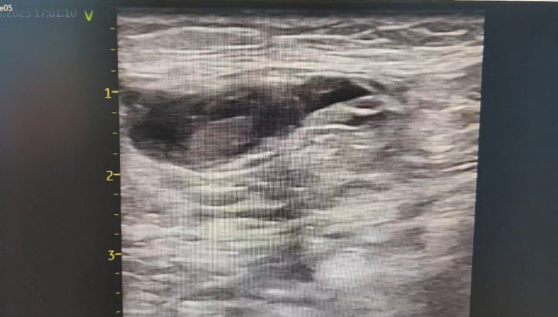

床旁超声检查提示:腹股沟区皮下可见特定范围的无回声区,边界清楚、形态欠规则,可见通道与动脉相连,动脉持续血流灌注;CDFI 示动脉与包块间分流口内可探及双向血流,包块内血流紊乱呈涡流,结合临床症状及检查结果,考虑为假性动脉瘤。

超声引导下凝血酶封堵术已成为临床处理假性动脉瘤的常用微创方式之一。该患者的手术过程顺利,在注射凝血酶 1 分钟后,超声复查显示瘤腔内活动血流消失,瘤体已血栓化,动脉与假性动脉瘤的通道封闭,听诊杂音及体表震颤感均消失。术后患者不适症状得到缓解,恢复顺利,次日出院(此为该患者个体恢复情况,不同患者因病情严重程度、体质、合并基础疾病等差异,恢复周期及效果可能不同)。